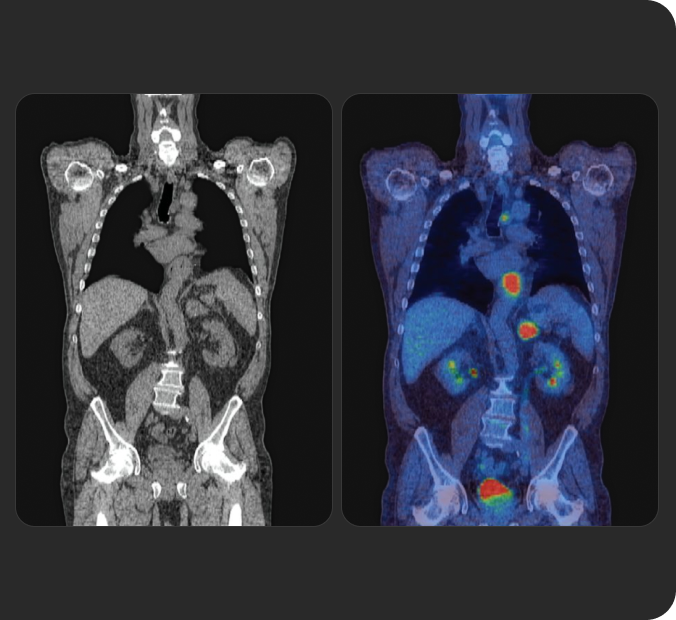

La Terapia con RadioLigandi (RLT) è un trattamento di precisione che rappresenta un'innovazione importante in ambito oncologico.

Scopri la RLT, le basi di questa forma di medicina di precisione e come Novartis sta gestendo la somministrazione continua della RLT ai pazienti in tutto il mondo.